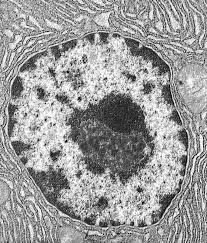

Aparición de la célula eucariota